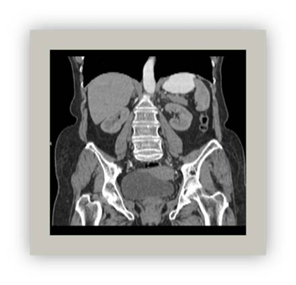

Multiplanar reconstruction (MPR)

These are 2D images reconstructed secondarily from volumetric data had during the study. New images can be achieved on any plane (axial, coronal, sagittal or any obliquity) (Figure 7).28

Figure 7 Coronal MPR multiplanar reconstruction.